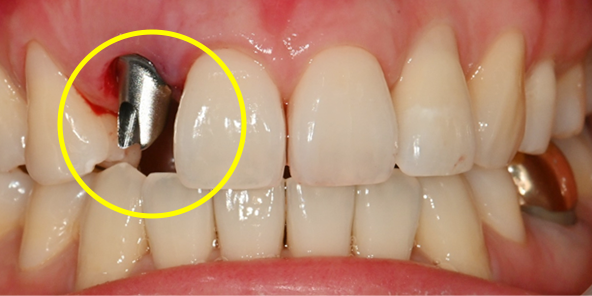

Before Treatment

After extraction, precise placement using surgical guide followed by pre-fabricated abutment connection

After extraction, precise placement using surgical guide,

followed by connection of

pre-fabricated abutment

Prosthesis completed on the day of surgery

Prosthesis completed on surgery day

After 2 months, replaced with final prosthesis if gingival contour changes or as needed

After 2 months, if gingival contour changes

or as needed, replaced with final prosthesis